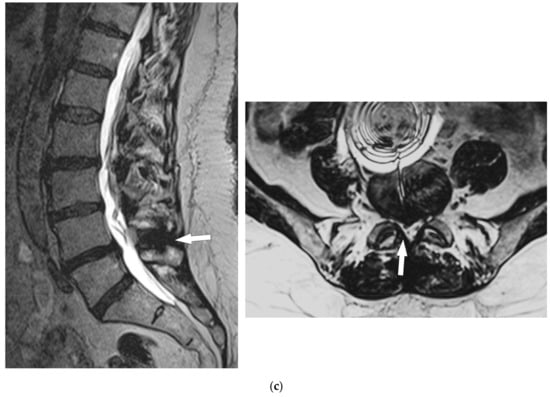

- Manfré, L. Posterior Arch Augmentation (Spinoplasty) before and after Single and Double Interspinous Spacer Introduction at the Same Level: Preventing and Treating the Failure? Interv Neuroradiol. 2014, 20, 626–631. [Google Scholar] [CrossRef]